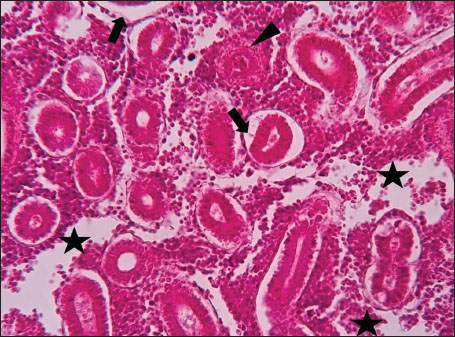

ABSTRACTBackground: The Mediterranean Sea has undergone significant ecological changes in recent decades, partly due to the introduction of non-native species. Lagocephalus sceleratus is an invasive Lessepsian species widely distributed in the Mediterranean, increasingly abundant along the Libyan coast, and potentially exposed to chronic environmental stressors. This species represents an important model for baseline pathological assessment in newly colonized marine environments. Aim: This study provides a descriptive histopathological assessment of kidney and gill tissues in adult L. sceleratus to document baseline tissue alterations without inferring direct environmental or pollution-related causation. Methods: A total of 150 adult specimens were collected from four Libyan coastal locations. Tissues were processed using standard histological techniques and evaluated semi-quantitatively (+, ++, +++) for lesion severity. Lesion severity grades were converted into ordinal numerical data and summarized using descriptive statistical approaches only. Results: Kidney tissues exhibited tubular degeneration, Bowman’s capsule dilatation, vascular congestion, extensive melanomacrophage centers (MMCs), and inflammatory lesions. Gill tissues showed disorganization of secondary lamellae, epithelial hyperplasia, edema, aneurysmal dilatations, vascular congestion, and MMC proliferation, some of which were associated with histologically observed parasitic structures. Conclusion: The observed alterations represent descriptive baseline tissue changes and should not be interpreted as direct evidence of pollution or specific environmental stressors. These findings provide reference data for future comparative pathological and ecological studies. Keywords: Lagocephalus sceleratus, Kidney, Gills, Histopathology, Melanomacrophage centers, Invasive species, Mediterranean Sea. IntroductionIn recent decades, the Mediterranean Sea has undergone profound ecological changes driven by the arrival and establishment of non-native marine species. Among these, Lagocephalus sceleratus has emerged as one of the most impactful Lessepsian migrants, due to its rapid geographic expansion, high ecological adaptability, and the presence of the potent neurotoxin tetrodotoxin in its tissues. This species has been widely documented to alter local fish communities, affect fisheries, and pose public health risks, making it an important target for biological and environmental assessment across the region (Katikou et al., 2022; Christidis et al., 2024). Fish are widely recognized as sensitive biological organisms in aquatic ecosystems, particularly in coastal habitats that are exposed to anthropogenic pressures such as industrial effluents, agricultural runoff, and untreated wastewater (Pinna et al., 2023). Among fish organs, the gills and kidneys are commonly regarded as sensitive to environmental stress, as they respond to physiological and pathological changes under environmentally suboptimal conditions. The gills, due to their large surface area and continuous exposure to surrounding water, are often the first tissues to exhibit structural alterations when fish encounter pollutants (Shahid et al., 2022). Histopathological changes in gills observed in polluted environments include epithelial lifting, lamellar fusion, hyperplasia, increased mucous cell density, and focal necrosis, which collectively reflect early physiological stress and potential compromise of respiratory function (Osman, 2010; Shahid et al., 2022). Similarly, the kidneys play crucial roles in osmoregulation, excretion of metabolic waste, and detoxification, making them highly vulnerable to chronic or systemic toxic effects (Wahidi et al., 2025). Documented renal lesions associated with chemical exposure include tubular deterioration, glomerular shrinkage, interstitial edema, and infiltration of inflammatory cells. These structural alterations often coincide with underlying biochemical disruptions, such as oxidative stress, impaired detoxification pathways, and activation of apoptotic mechanisms (Bernet et al., 1999; Authman, 2015). Despite the growing body of research on the ecological and toxicological implications of L. sceleratus, detailed histopathological assessments of this species remain scarce, especially in the southern Mediterranean basin, where environmental conditions and pollution profiles may differ from those in other regions. To date, detailed tissue-level studies of L. sceleratus from the southern Mediterranean are lacking, which limits the understanding of how this invasive species responds physiologically to local environmental stressors (Shakman et al., 2019; Ulman et al., 2021; Mohmmed et al., 2023). Accordingly, the present study aims to provide a comprehensive descriptive evaluation of histopathological changes in the kidneys and gills of L. sceleratus. The study is designed as a baseline histopathological assessment, focusing on tissue-level alterations without establishing causal links to environmental pollution or physicochemical stressors. By documenting structural aberrations and pathological features, this study contributes reference data for future monitoring and comparative studies in Mediterranean coastal ecosystems. Materials and MethodsSample designA total of 150 adult specimens of L. sceleratus, including both sexes, were collected from four Libyan coastal locations: Talamitha (n=39), Susah (n=34), Ain El-Ghazala (n=30), and Khalij Al-Bambah (n=47). Fish ranged in total length from 51 to 66 cm and in weight from 1.5 to 3.5 kg. Only apparently healthy adults were included, while juveniles were excluded to avoid age-related histopathological variation. Sampling was conducted opportunistically with assistance from local fishermen. All specimens were collected within a comparable seasonal window to minimize seasonal histopathological variability. Sex was recorded when possible; however, sex-based histopathological comparisons were not performed, as this was beyond the descriptive scope of the study. Fish were transported on ice at +4°C and examined in the Pathology Laboratory, Faculty of Veterinary Medicine, Omar Al-Mukhtar University (Mohmmed et al., 2023). Specimens were collected from a range of depths (0.5–70 m), with the majority from shallow waters (<10 m) and a subset (approximately 50 fish) from deeper locations (>30 m). Environmental physicochemical parameters such as temperature, salinity, and dissolved oxygen were not measured; therefore, no direct associations between histopathological findings and environmental variables were assessed. Tissue processing and histopathological examinationTissue specimens were fixed in 10% neutral buffered formalin for 24 hours. Following fixation, the samples were transferred to 70% ethanol for storage at room temperature. Subsequently, the tissues were processed for routine histopathological examination following standard procedures (Paul and Chanda, 2017). Paraffin embedding was performed, and 5 µm-thick sections were prepared using a microtome. Sections were stained with hematoxylin and eosin (H&E) and examined under a light microscope. Photomicrographs of representative lesions were captured using a high-resolution digital camera. Histopathological alterations were evaluated using a semi-quantitative scoring system adapted from Hose et al. (1996), Moshaie-Nezhad et al. (2021), and Alshailabi et al. (2023), where lesion severity was graded as mild (+), moderate (++), or severe (+++). Lesion severity grades (+, ++, +++) were converted into ordinal numerical values (1–3) for descriptive summarization of lesion severity. Due to the descriptive baseline nature of the study and the absence of a reference control group, inferential statistical comparisons were not emphasized or applied. Lesion severity scores were therefore summarized descriptively to avoid overinterpretation of the findings. Scoring was performed independently by two experienced observers, and representative lesions were confirmed across three sections per organ to ensure consistency. Tissues with visible parasitic structures were described separately from non-parasitized tissues to avoid conflating parasite-associated lesions with non-specific tissue alterations. The functional implications of the observed lesions were interpreted in accordance with Flores-Lopes and Thomaz (2011). Ethical approvalAll animal experiments conducted in this study were approved by the Ministry of Higher Education & Scientific Research and the Libyan National Committee for Biosafety & Bioethics, Libya. All procedures were performed in accordance with the relevant ethical guidelines, with session number 21/CH/25, dated 26/05/2021. ResultsHistopathological examination of the kidneyHistopathological examination of the kidney tissues of L. sceleratus revealed multiple alterations. Prominent melanomacrophage centers (MMCs), necrotic areas, dilatation of Bowman’s capsules, and vacuolar degeneration were observed (Fig. 1), associated with interstitial lymphohematopoietic tissue (Fig. 2). Dilated and congested blood vessels and extensive MMCs were also noted (Fig. 3). Renal degeneration surrounding lymphohematopoietic tissue, large clusters of MMCs, and thickened, congested vessel walls within fibrotic areas were evident (Fig. 4). Atrophic renal degeneration with necrotic and vacuolar changes was observed (Fig. 5). Severe inflammatory infiltration of lymphatic cells and granulomas with necrotic centers, surrounded by fibrous tissue, was detected (Figs. 6–7).

Fig. 7. Histopathology of the kidney in an adult L. sceleratus showed the atrophic renal degeneration (stars), dilatation of Bowman’s capsules (thick arrows), and a granuloma (head arrow). ×400 H&E. Histopathological examination of the gillsThe gill sections of adult L. sceleratus exhibited multiple structural alterations. Secondary lamellae showed marked disorganization, while gill filaments displayed club-shaped deformities and occasional aneurysmal dilatations (Fig. 8). Vascular congestion with telangiectatic changes and proliferation of MMCs were also observed (Figs. 9–10). Edematous changes in primary lamellae, separation of the epithelial layer, lamellar aneurysms, and epithelial hyperplasia were documented (Figs. 10–11). Focal damage to secondary lamellae, disruption of lamellar architecture, presence of lamellar aneurysms, and unidentified parasitic structures were observed (Fig. 12). Pronounced vascular congestion and dilatation of lamellae due to red blood cell accumulation were noted (Fig. 13).

Fig. 8. Histopathology of the gills in an adult L. sceleratus showing disorganization of secondary lamellae (thick arrows), club-shaped filament deformities with aneurysms (thin arrows), and congestion/telangiectasia in filament vessels (stars). ×40 H&E.

Fig. 9. Histopathology of the gills in an adult L. sceleratus showing the disorganized secondary lamellae (thick arrows), MMCs (thin arrows), and vascular congestion/telangiectasia in filaments (stars). ×40 H&E.

Fig. 10. Histopathology of the gills in an adult L. sceleratus showing the edema in primary lamellae and epithelial detachment (thin arrows), lamellar aneurysm with MMCs (thick arrows), and congestion/telangiectasia (stars). ×40 H&E.

Fig. 11. Histopathology of the gills in an adult L. sceleratus showing edema in primary lamellae and epithelial detachment (thin arrow), curling of secondary lamellae (head arrows), congestion/telangiectasia (star), and epithelial hyperplasia (thick arrows). ×40 H&E.